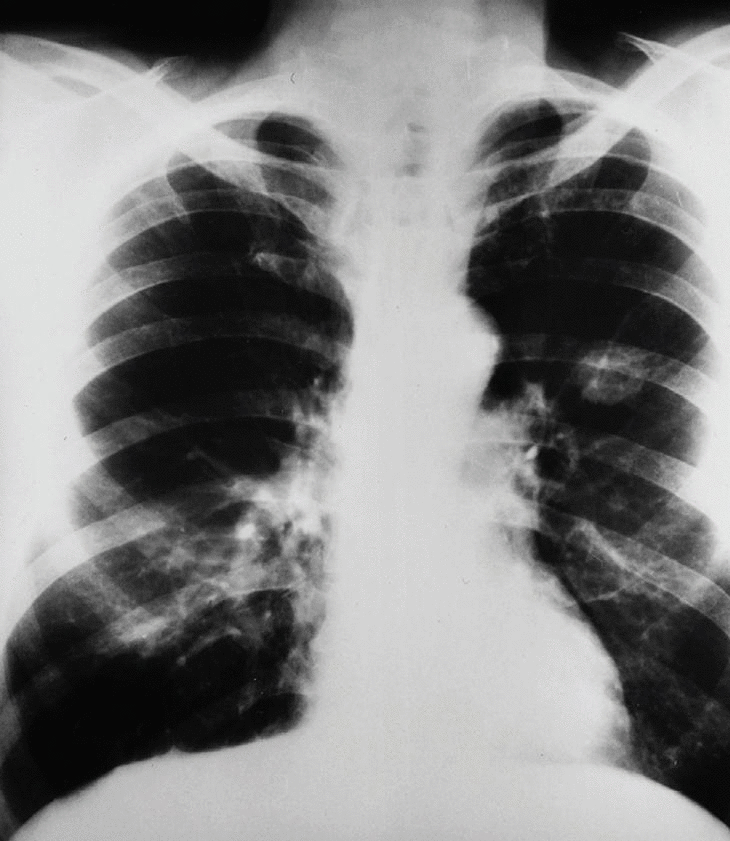

El paciente acusa además dolor en manos y piernas, por lo que se le realizan radiografías anteroposteriores de dichas regiones donde se observa intensa reacción perióstica ondulante en tibias, peronés, metacarpianos y falanges, compatible con osteoartropatía hipertrófica pneúmica (OAH) (figs. 2 y 3).

Fig. 2

Fig. 3

La OAH se caracteriza radiológicamente por una elevación del periostio con depósito neoformado debajo del mismo y resorción del hueso endostial. Suele ocurrir en extremos distales de metacarpianos, metatarsianos y huesos largos (figs. 2 y 3).